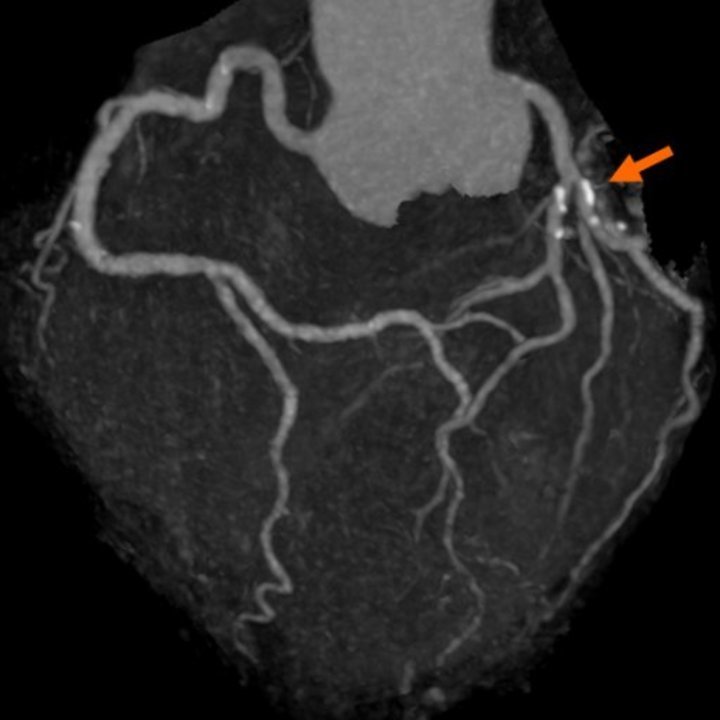

Анатомия коронарных артерий: КТ-изображения